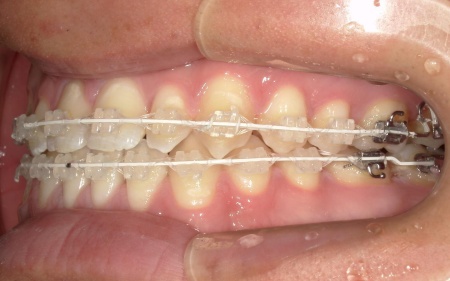

②白色(セラミック)のブラケットとホワイトワイヤーを用いたセラミックブラケット矯正

矯正の方法は①と同様ですが、装置の色味が異なります。

メリット:装置が白いため歯の色に馴染みやすく、目立ちにくい

患者様は「できるだけ目立ちにくい装置を使用したい」とのことから、②のセラミックブラケット矯正を選択されました。

まず、下奥歯(臼歯)を歯茎の外側に持ち上げる「挺出(ていしゅつ)」という処置を行いました。

奥歯が少し高くなることで、下顎全体がわずかに後ろへ動くため、前歯の噛み合わせが整いやすくなります。